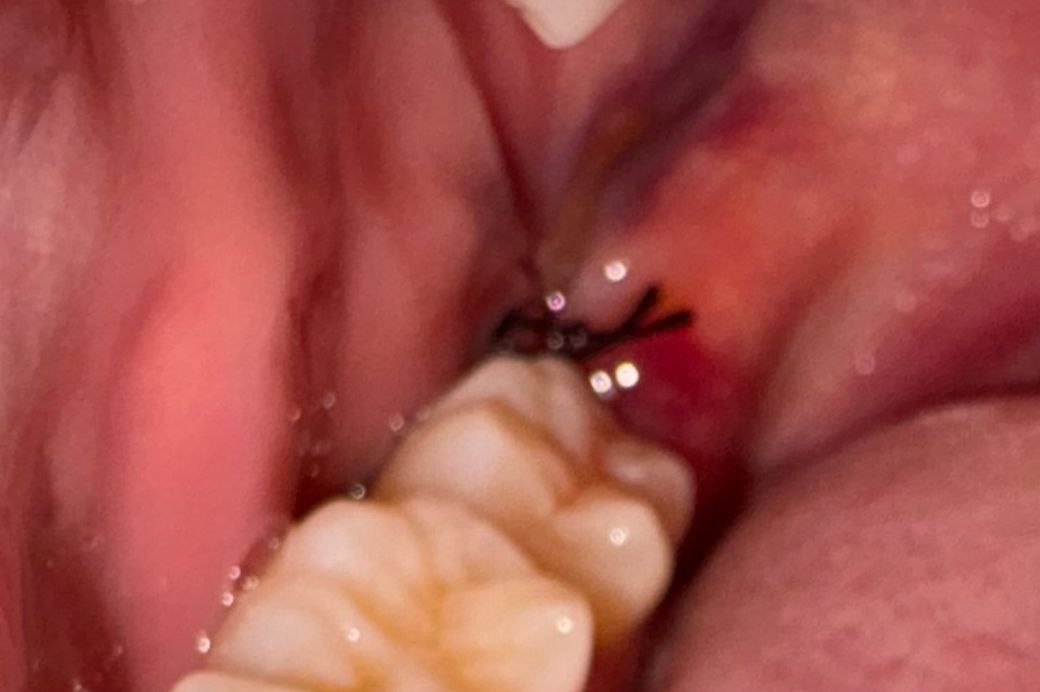

완전매복사랑니 발취했는데 잘 아물고있는건가요??

사진상으로 사랑니 발치를 한곳은 잘 아물고 잇으니 너무 걱정하지 않으셔도 될것같습니다.

사진이 흐려서 정확하게 확인이 되진 않습니다. 특별한 통증이 없거나 냄새가 나지 않는다면 문제가 없이 아물고 있을 가능성이 높습니다.

자세한 확인을 위해서 치과에서 진료를 받아보는 것을 권유드립니다.

사진은 발치부위가 잘 안보여서 확인이 어렵네요

봉합은 안풀리고 잘 되어 있고요

주의사항 잘 지키시면 잘 아물것 같습니다